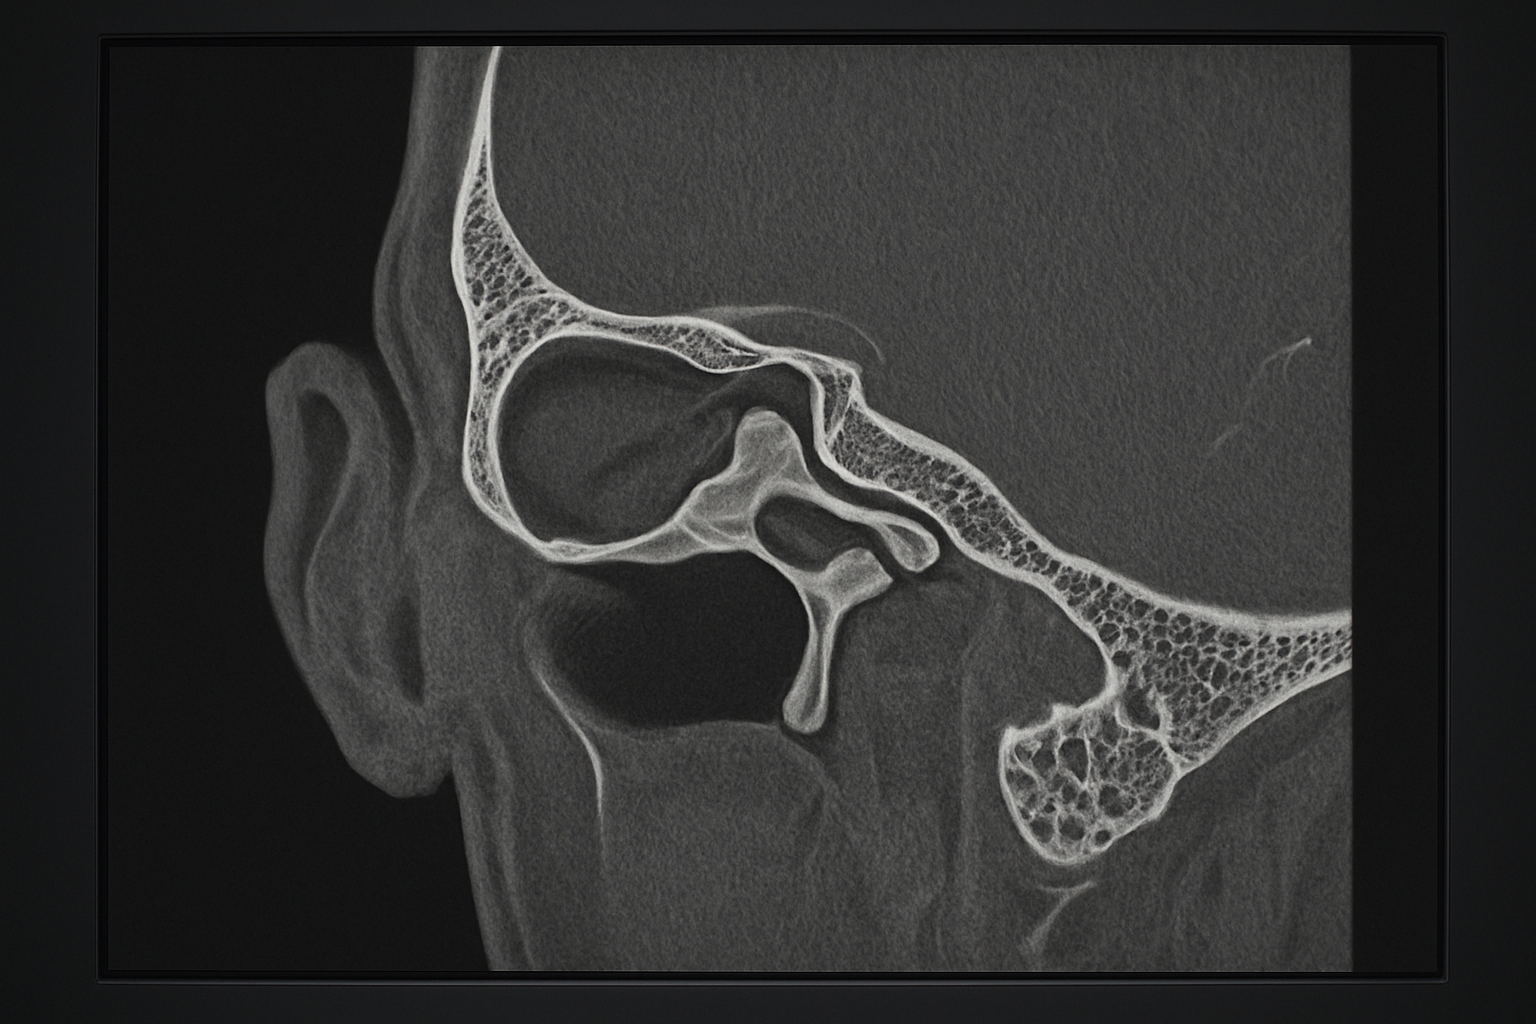

HRCT temporal bone scans provide unmatched detail of the ear’s complex anatomy, from the tiny ossicles in the middle ear to the delicate labyrinthine structures of the inner ear. Understanding these anatomical landmarks is essential for identifying pathology and guiding treatment decisions.

We’ll explore the external and middle ear structures you’ll encounter on every HRCT ear anatomy study, including the tympanic membrane, ossicular chain, and mastoid air cells. You’ll also learn to recognize the intricate inner ear complex anatomy, including the cochlea, semicircular canals, and internal auditory canal. Finally, we’ll cover common pathological findings and how to apply clinical interpretation guidelines that will enhance your temporal bone radiology skills.

HRCT ear anatomy clearly demonstrates the ossicular chain within the middle ear space. The malleus head appears in the epitympanum, connected to the incus body through the incudomalleolar joint. The long process of the incus extends inferiorly to articulate with the stapes head through the incudostapedial joint. The stapes footplate sits within the oval window, creating the connection between the middle and inner ear spaces.

The superior spatial resolution of HRCT temporal bone imaging reaches approximately 0.1 to 0.2 millimeters, making it possible to clearly distinguish individual ossicles within the middle ear cavity. The malleus, incus, and stapes become distinctly visible, along with their articulations and surrounding soft tissue relationships. Standard CT simply cannot achieve this level of detail due to its inherent technical limitations.